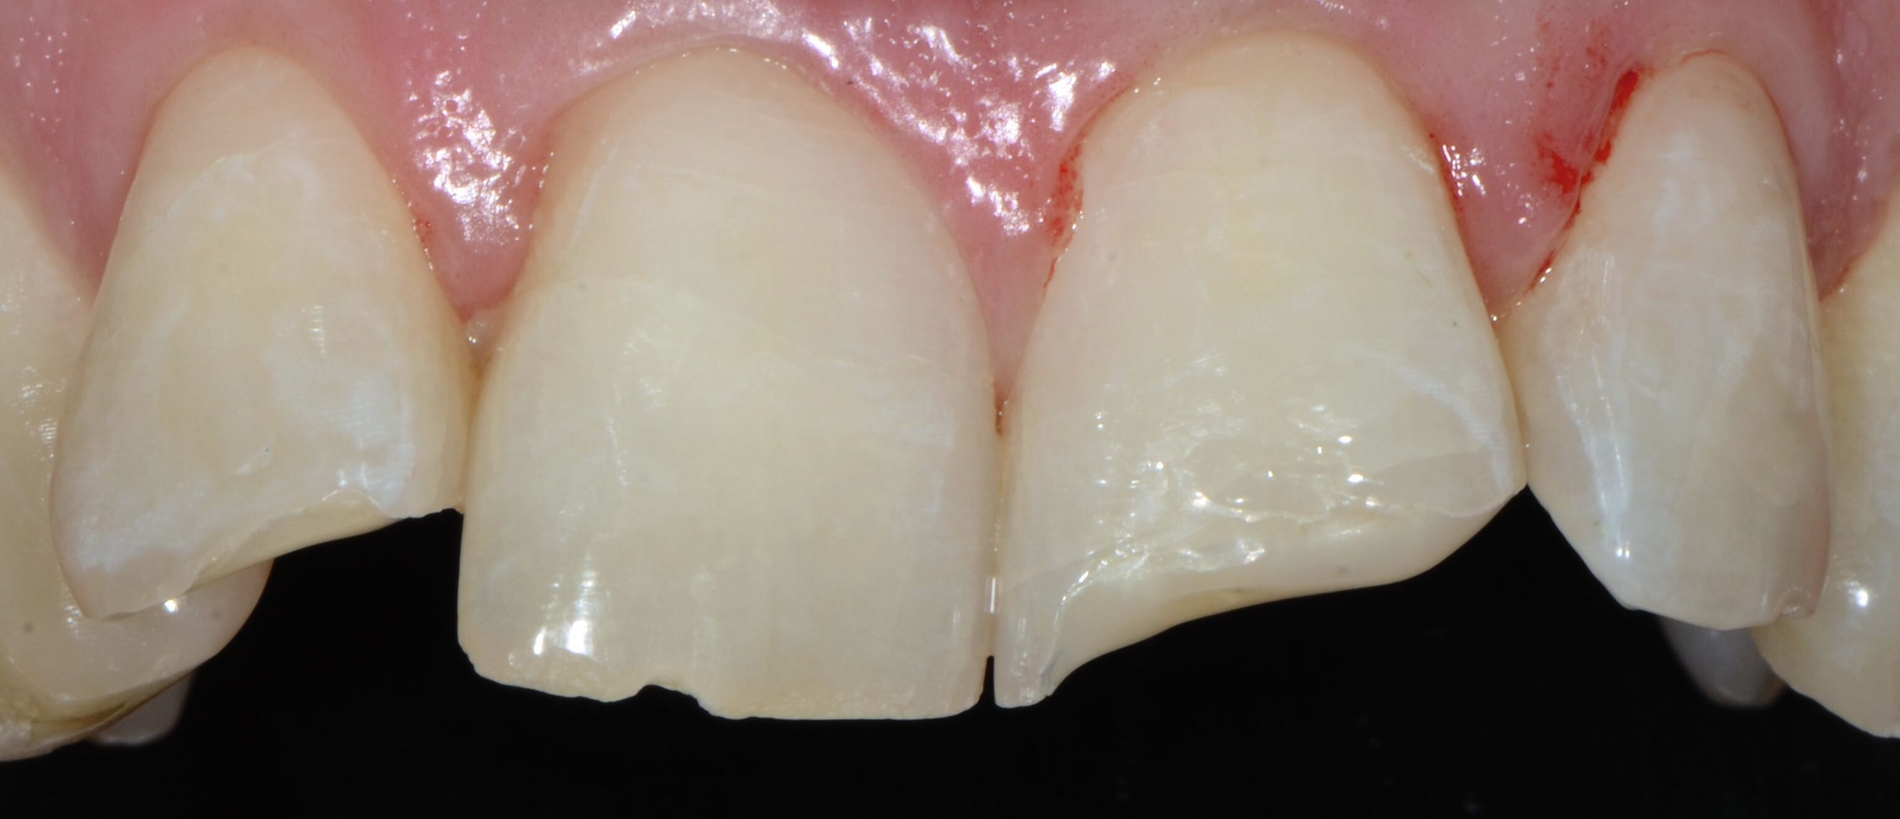

Die zahnärztliche Befundung ergibt koronale Schmelz- und Dentinfrakturen ohne Pulpaexposition an den Zähnen 12 und 21. An Zahn 11 liegt eine ausgeprägtere subgingivale Kronenfraktur vor. Auf dem Weg zur Uniklinik bemerkte der Patient das gelockerte Fragment an Zahn 11, entfernte es selbstständig und lagerte es trocken in einem Taschentuch. Trotz der Nähe der Fraktur zur Pulpa des Zahnes 11 ist diese nicht eröffnet (Abbildung 1).

Das Ziel der Erstversorgung nach Trauma sollte darin bestehen, freiliegende Dentinwunden abzudecken, um eine bakterielle Infektion des Endodonts zu verhindern [Herrmann et al., 2023]. Da die Fragmente der Zähne 12 und 21 nicht auffindbar waren, wird das freiliegende Dentin der beiden Zähne zunächst mit einer adhäsiven Schicht aus Flow Komposit abgedeckt. An Zahn 11 ist das Fragment intakt und repositionierbar, daher kann eine restaurative Versorgung durch adhäsives Reattachment erreicht werden.